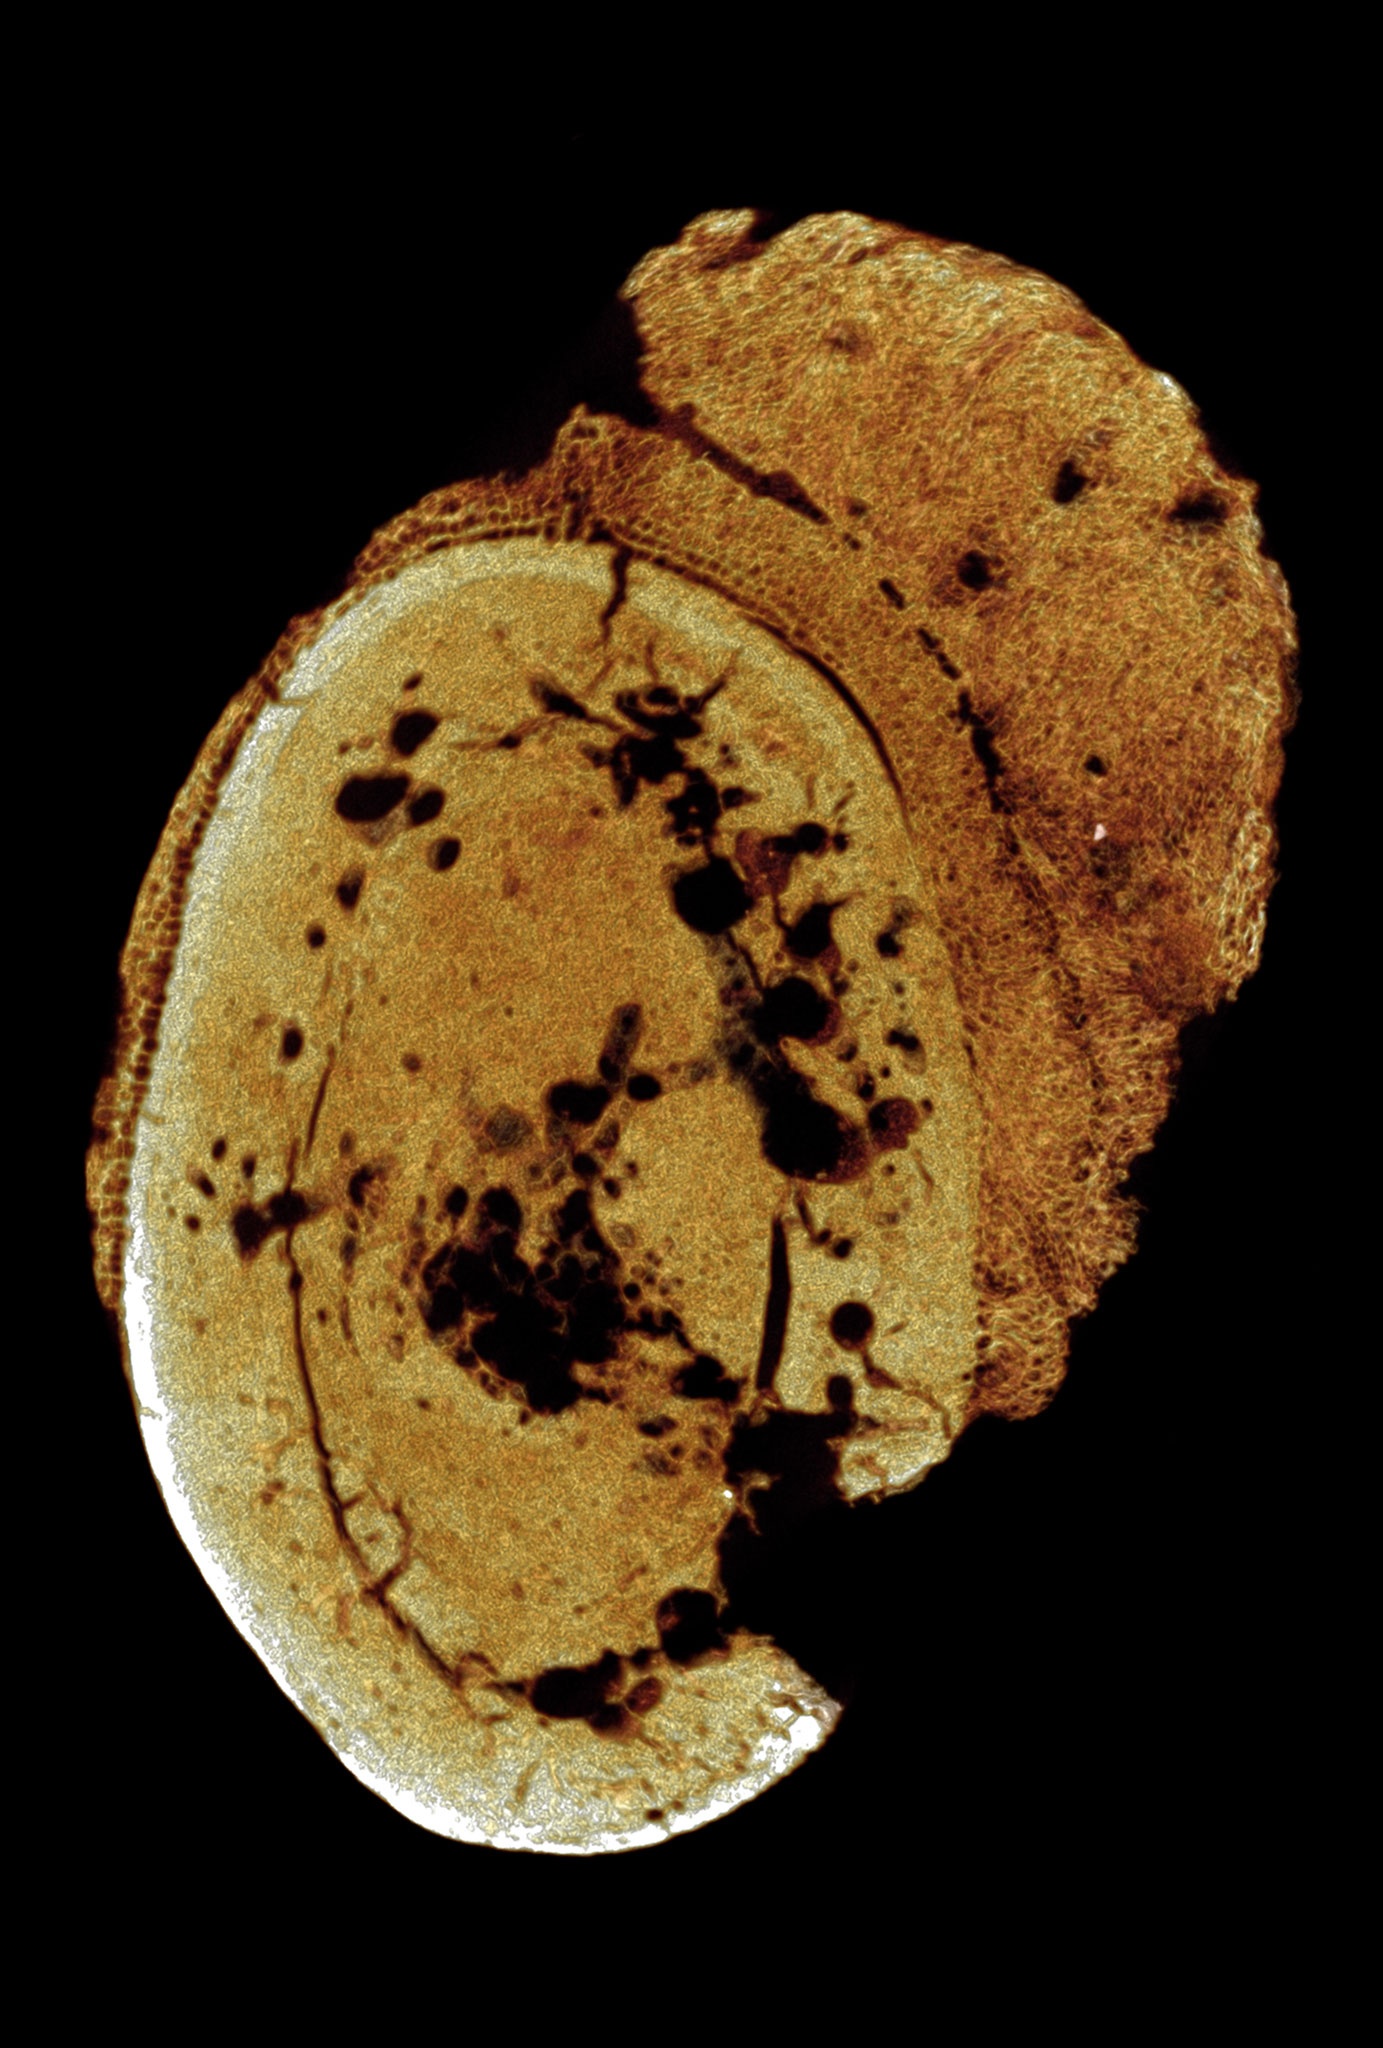

Hình ảnh 3D dựng lại hóa thạch xương người có niên đại hàng triệu năm, chứa tế bào ung thư sớm nhất thế giới. Ảnh: Patrick Randolph-Quinney, UCLAN.

Sử dụng phương pháp micro-CT, nhóm tác giả từ Đại học Witwatersrand đã nghiên cứu chi tiết hình ảnh 2 chiều và 3 chiều bên trong hóa thạch. Hình ảnh đã ghi lại được sự khác biệt ở mật độ xương và các mảnh vỡ bên trong.

Hóa thạch xương có mô hình tăng trưởng bất thường, điển hình như hình dạng bên ngoài giống như súp lơ. Đặc điểm này nhóm nghiên cứu chẩn đoán bệnh nhân mắc bệnh u xương ác tính - căn bệnh ảnh hưởng nhiều đến trẻ em và thanh niên ngày nay.

Bằng cách dựng lại hình ảnh 3D của các tế bào ung thư Osteosarcoma, nhóm nghiên cứu tiếp tục làm dấy lên cuộc tranh luận về nguồn gốc chính xác của bệnh ung thư. Cho đến ngày nay, con người vẫn chưa thể lý giải được căn bệnh này.

Hóa thạch xương mang tế bào ung thư giống với cấu trúc xương người hiện đại. Ảnh: Patrick Randolph-Quinney, UCLAN.